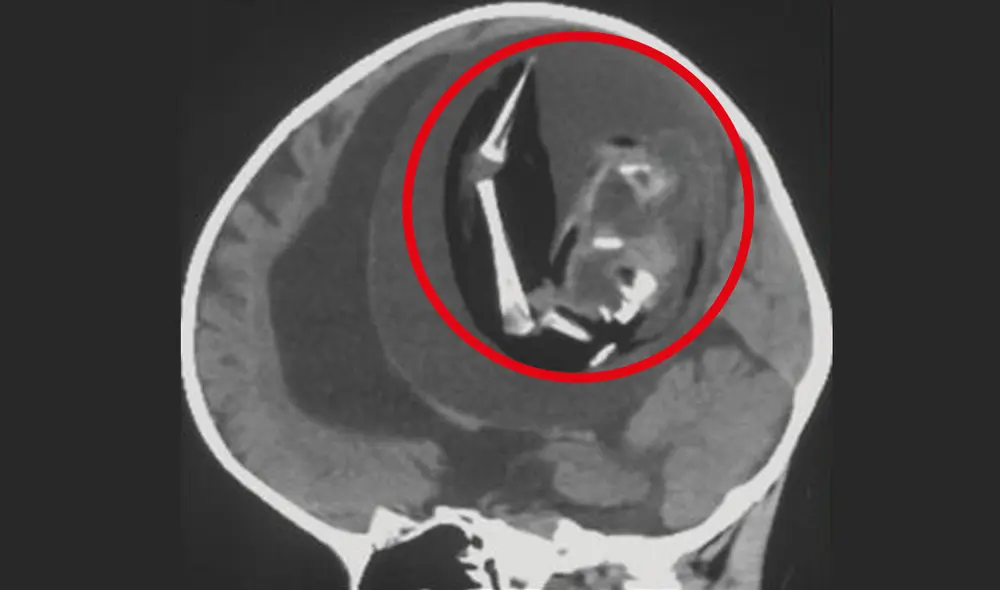

Los escáneres cerebrales de la cabeza del niño de 1 año muestran que el feto contenía una columna vertebral, un fémur y una tibia (dos huesos de la pierna). Asimismo, tenía espina bífida, una afección en la que parte de la médula espinal queda expuesta, en lugar de estar cubierto por tejidos de la espalda debido a un problema durante el desarrollo.

Una vez extraído, también se determinó que el engendro tenía "brotes en forma de extremidades superiores y dedos".